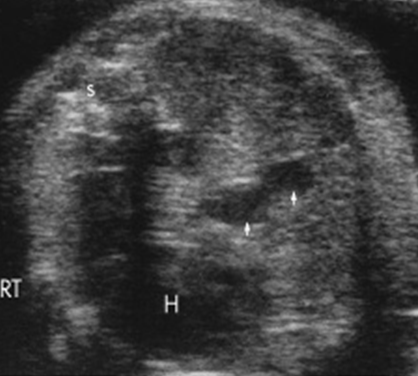

4 chamber view

Normal 4 chamber view

Identify structures of the heart